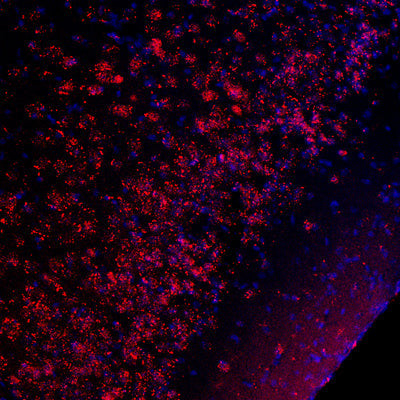

Anti-Phospho-CREB1-Ser133 antibody (STJA0003605)

| Short Description | Rabbit polyclonal anti-Phospho-CREB-Ser133 for use in WB and IHC in Mouse, Rat, Bovine, Canine, Chicken, Human, Non-Human Primates, Sheep, Xenopus and Zebrafish samples. Datasheet included with dilution recommendations, and related reagents. |

| Applications | WB/IHC |

| Dilution Range | WB 1:1000IHC 1:100-1:1000 |